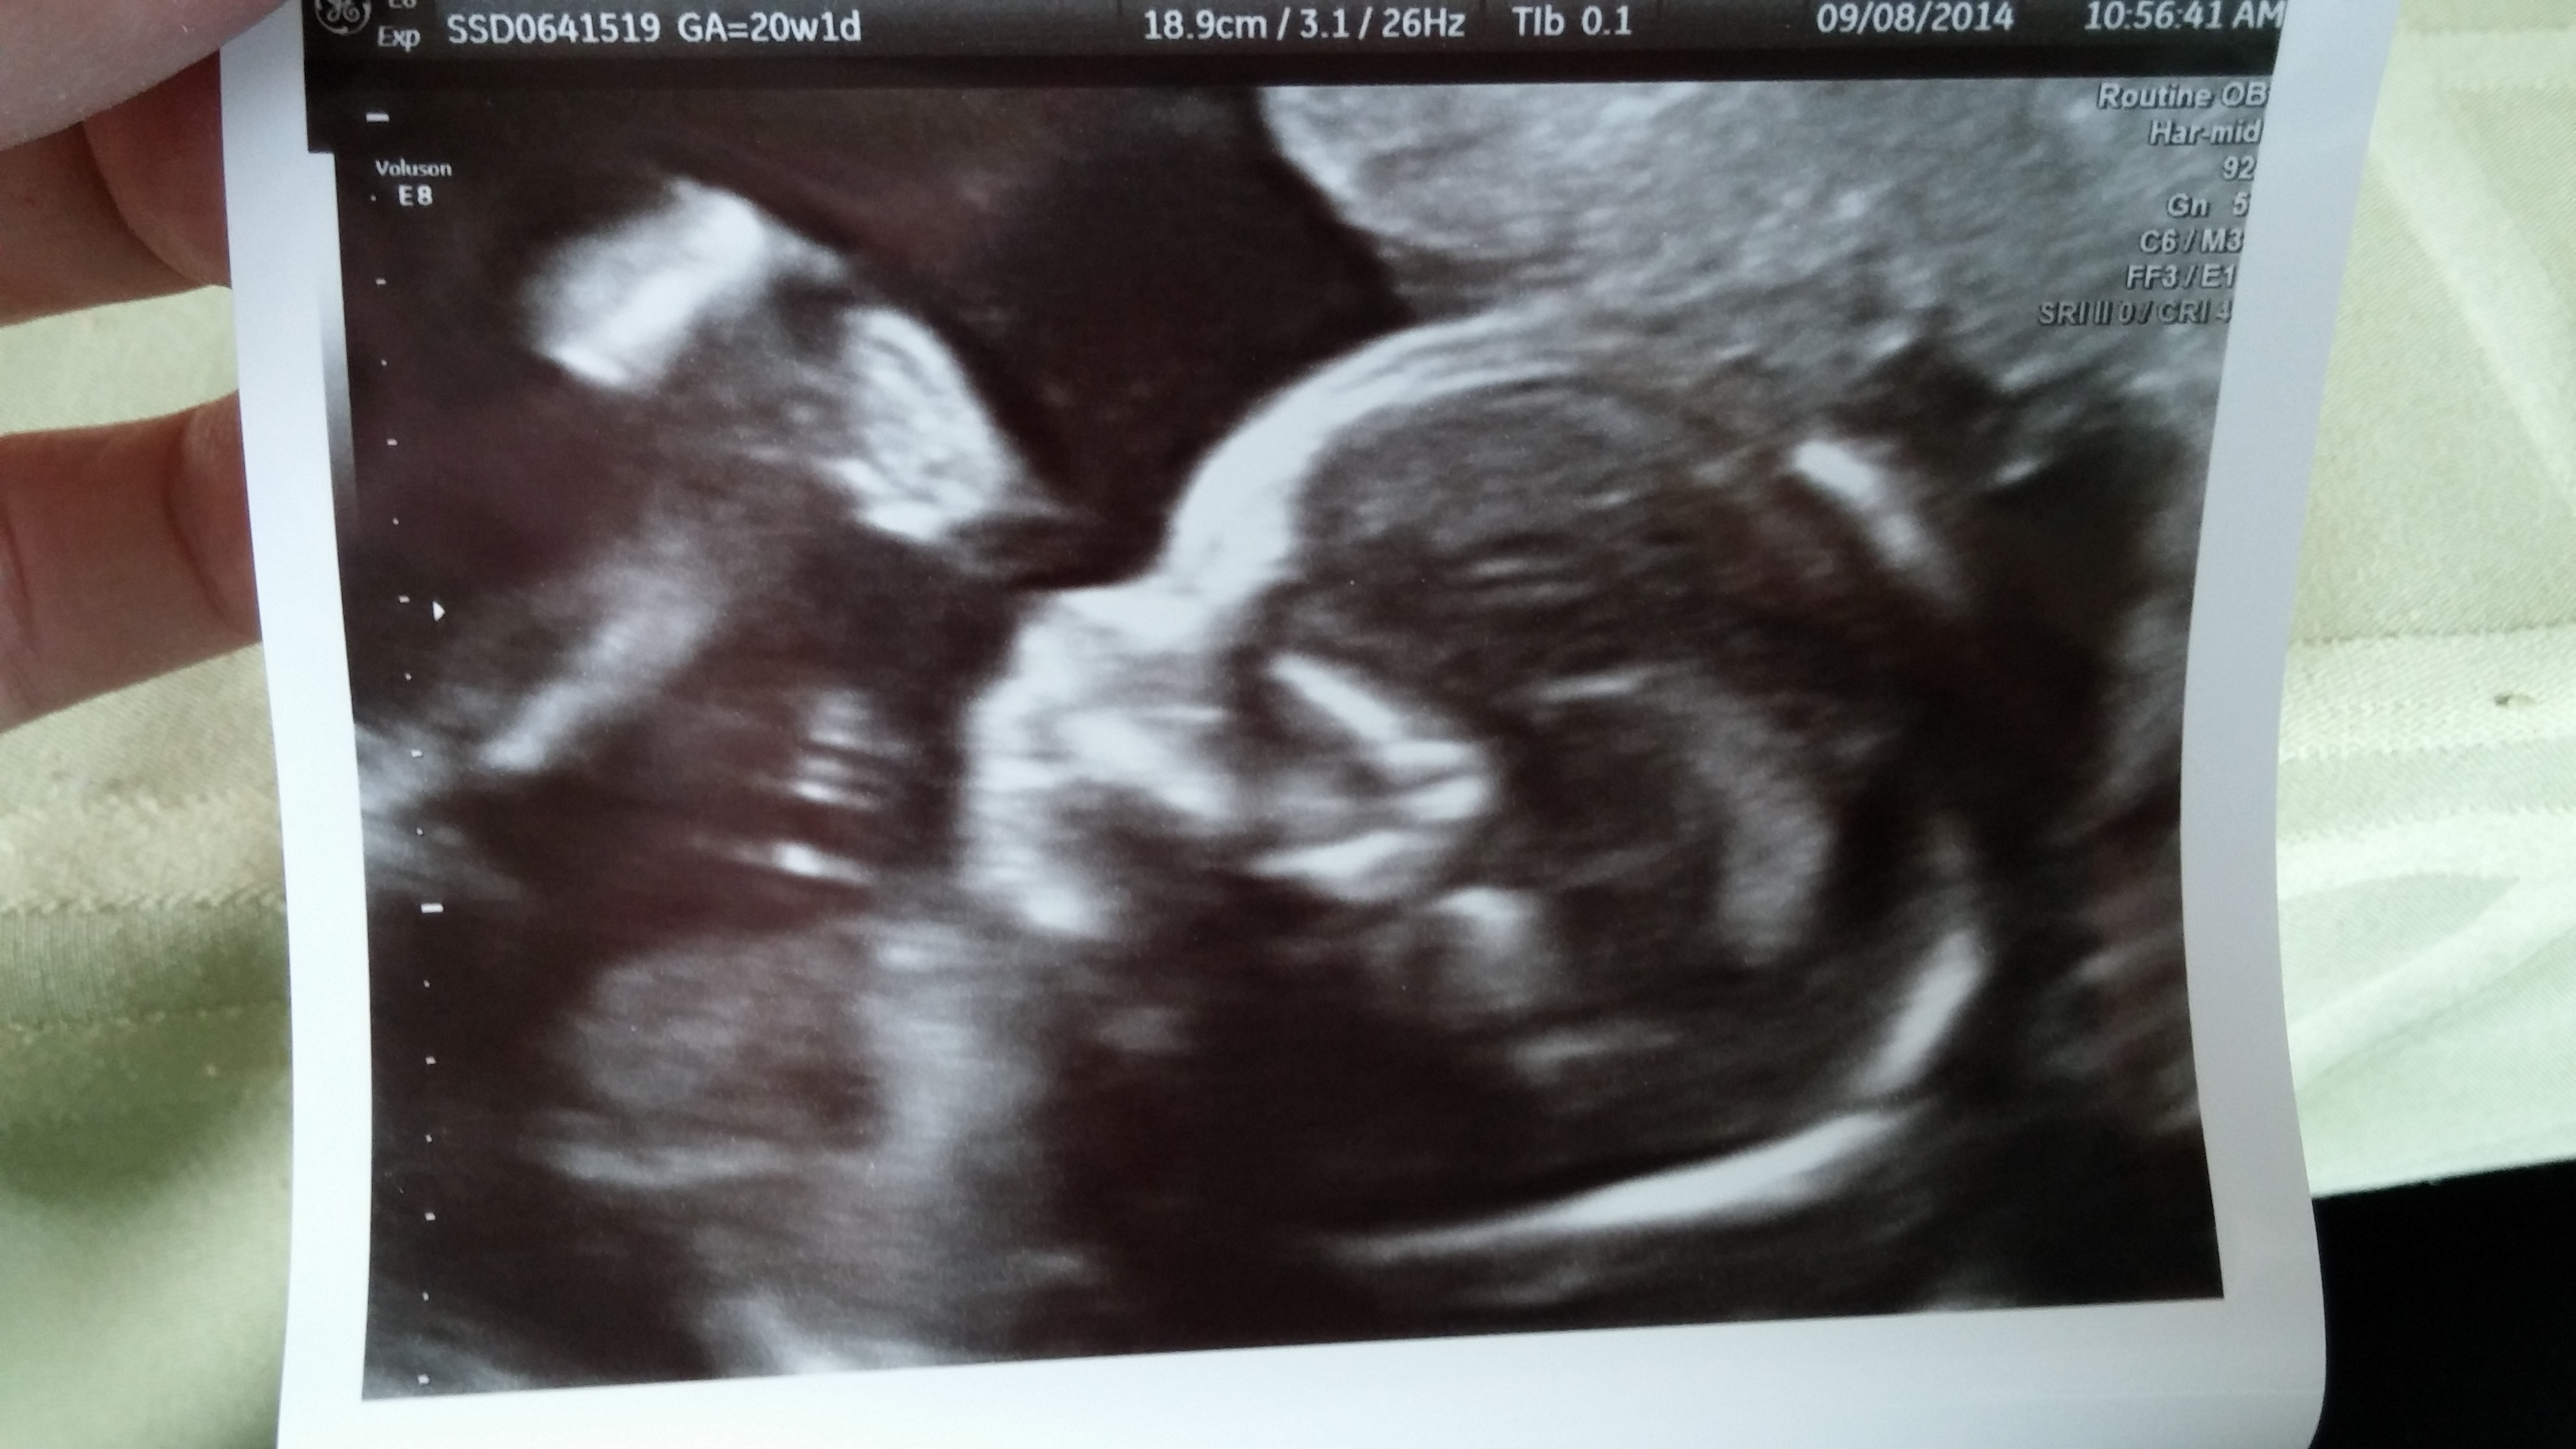

20w - A/S photo from this morning! It's a Girl!!